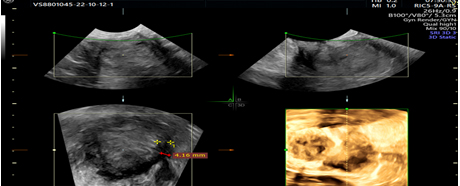

Picture 2. 3D ultrasonographic view of interrupted endometrial myometrial junction, green cursor.

Picture 3. 2D and 3D ultrasonographic images with heterogeneous endometrium.

The possibilities of 3D ultrasonography, such as volume computerized imaging, computerizedultrasonographic tomography and rendering, can help assess myometrial and cervical invasion (Picture 3) (24).